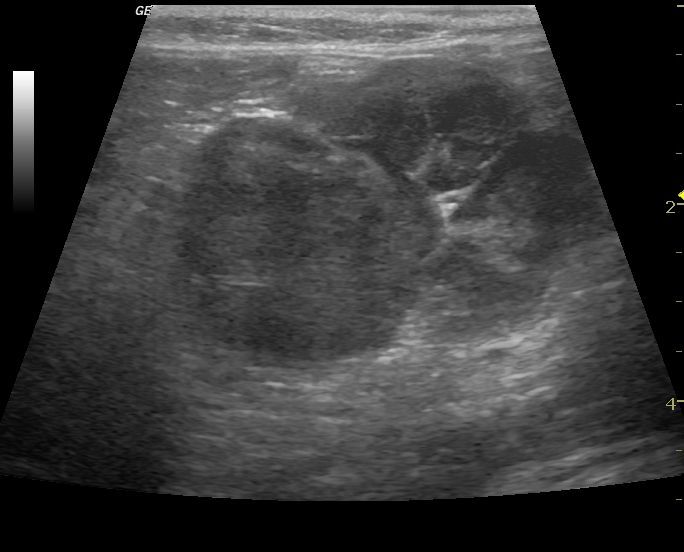

La ecocardiografía es una herramienta imprescindible en el diagnóstico y seguimiento de las patologías cardíacas, tanto congénitas como adquiridas, ya que nos permite visualizar el interior de corazón, pudiendo observar sus paredes, sus válvulas y aportando datos objetivos sobre la funcionalidad cardíaca. Además la ecocardiografía Doppler, (Doppler espectral, pulsado y continuo, y Doppler de flujo color) permite la evaluación de la dirección y la velocidad del flujo sanguíneo a traves del corazón y de los grandes vasos.